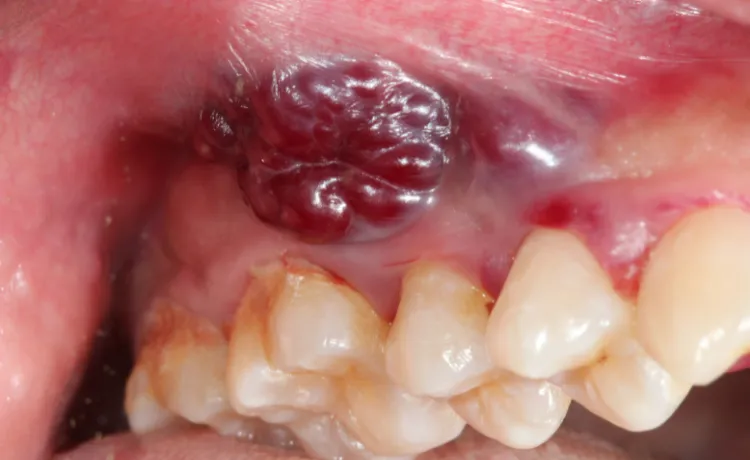

Guzek, zgrubienie, narośl: Kiedy nierówna powierzchnia to powód do niepokoju?

Innym niepokojącym objawem jest pojawienie się guzka, zgrubienia lub narośli. Może to być wyczuwalne zgrubienie na wardze, języku, dnie jamy ustnej, wewnętrznej stronie policzka lub na dziąśle. Czasem ma nieregularną, kalafiorowatą strukturę. Takie zmiany mogą być twarde w dotyku i rosnąć, co jest silnym sygnałem do natychmiastowej wizyty u specjalisty.